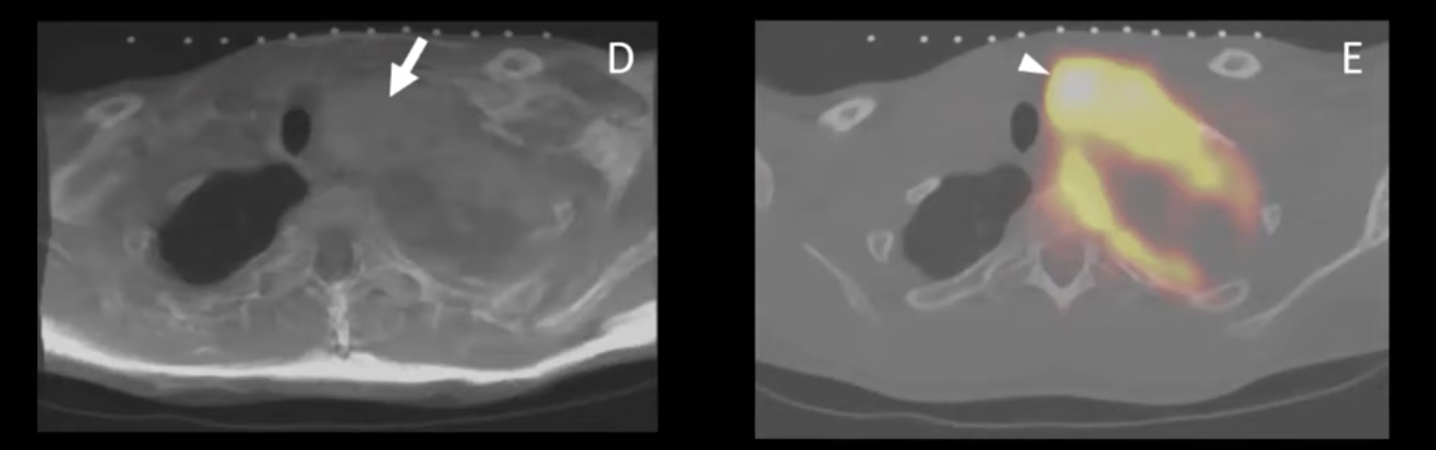

Nikhil Gowda presented the potential use of IGTFusion in needle placement during CT-guided biopsy of a neurofibroma during the 11th National Image Guided Therapy Workshop (https://ncigt.org/igt-virtual). The active lesion was FDG-avid in PET and the MR image showed corresponding heterogeneity, but the procedural CT failed to differentiate the active lesion from the remainder of the tumor. A 3D, triple-modality (MR, PET, CT) fusion with IGTFusion would have made the biopsy more precise and less challenging.